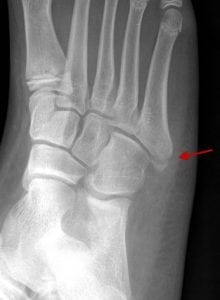

2. What is the diagnosis for the image below?

3. Which is more likely to result in non-union: a fracture of the proximal 5th metatarsal diaphysis, or an avulsion fracture of the tip of the 5th metatarsal at the attachment site of the peroneus brevis tendon?